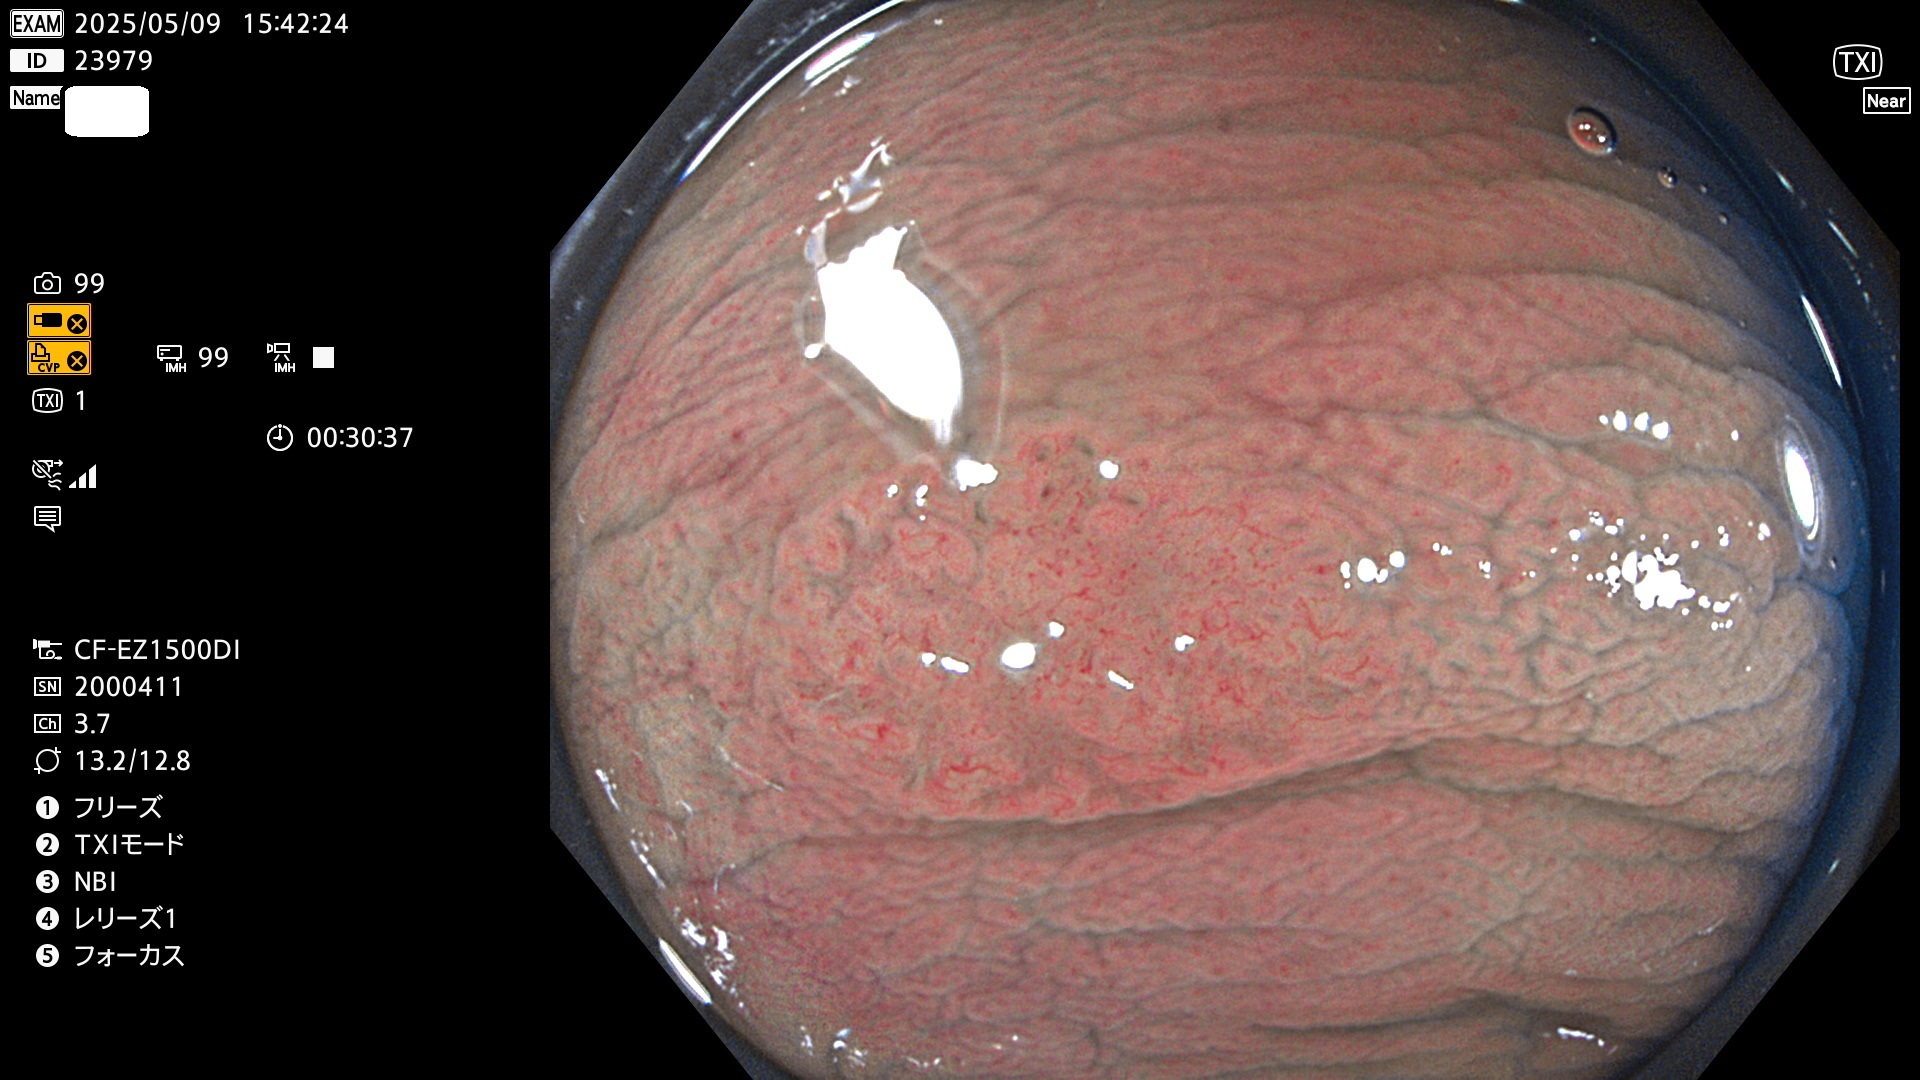

完全に平坦な物をUb、陥凹している物をUcと呼びます。Ubは認識が困難で、Ucはびらん(炎症)と紛らわしいために見落とされやすく、「内視鏡後・大腸癌」の原因になります。

抽出の対象期間 2025年5月8日〜5月11日の4日間(48件の検査)14個 (14/48=29%)